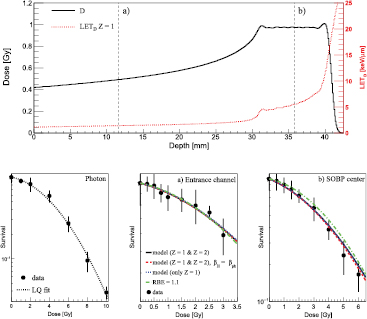

3.2. Comparison with experimental data

The first experimental configuration studied in this work is shown in the upper panel of figure 2, where FLUKA-calculated depth–dose and depth–LETD distributions are displayed. The positions in the EC and in the middle of the SOBP, where the RENCA cell survival as a function of the proton dose has been measured, are marked with a and b, respectively. The measured reference photon clonogenic data as a function of the photon dose are shown in the lower-left panel of figure 2 together with the performed LQ fit. The resulting best-fit LQ parameters are reported in table 3. In the other two lower panels marked with (a) and (b), clonogenic data as a function of proton dose in EC and in the middle of the SOBP are compared against model predictions and the results obtained assuming an RBE of 1.1. Qualitatively comparing model outcomes and the experimental data, all the calculations presented seemed to reproduce, within the error bars, the clonogenic data. Keeping in mind the experimental uncertainties, both the full calculations and those considering biologically only Z = 1 particles give similar levels of agreement. Assuming for both H and He particles  instead of a LET-dependent β term seemed to slightly improve the agreement for the high dose region (>3 Gy) for the middle of the SOBP configuration. The calculations performed assuming a constant RBE of 1.1 appeared to overestimate the survival for the middle SOBP set-up, where an experimental RBE value at 2 Gy photon dose of about 1.3 has been found.

instead of a LET-dependent β term seemed to slightly improve the agreement for the high dose region (>3 Gy) for the middle of the SOBP configuration. The calculations performed assuming a constant RBE of 1.1 appeared to overestimate the survival for the middle SOBP set-up, where an experimental RBE value at 2 Gy photon dose of about 1.3 has been found.

Figure 2. Upper panel: dose values (solid line) as a function of depth in water are plotted together with the LETD values for Z = 1 particles (dotted line). The positions in the EC and in the middle of the SOBP where the RENCA cell survival as a function of the proton dose has been measured are marked with (a) and (b), respectively. Lower-left panel: measured reference photon RENCA clonogenic data (points with error bars) as a function of the photon dose are shown together with the performed LQ fit. Lower-center panel: measured RENCA clonogenic data (points with error bars) as a function of the proton dose are shown together with the model predictions (lines), as reported in the legend, for the EC configuration. Lower-right panel: measured RENCA clonogenic data (points with error bars) as a function of the proton dose are shown together with the model predictions (lines) for the middle of the SOBP configuration.